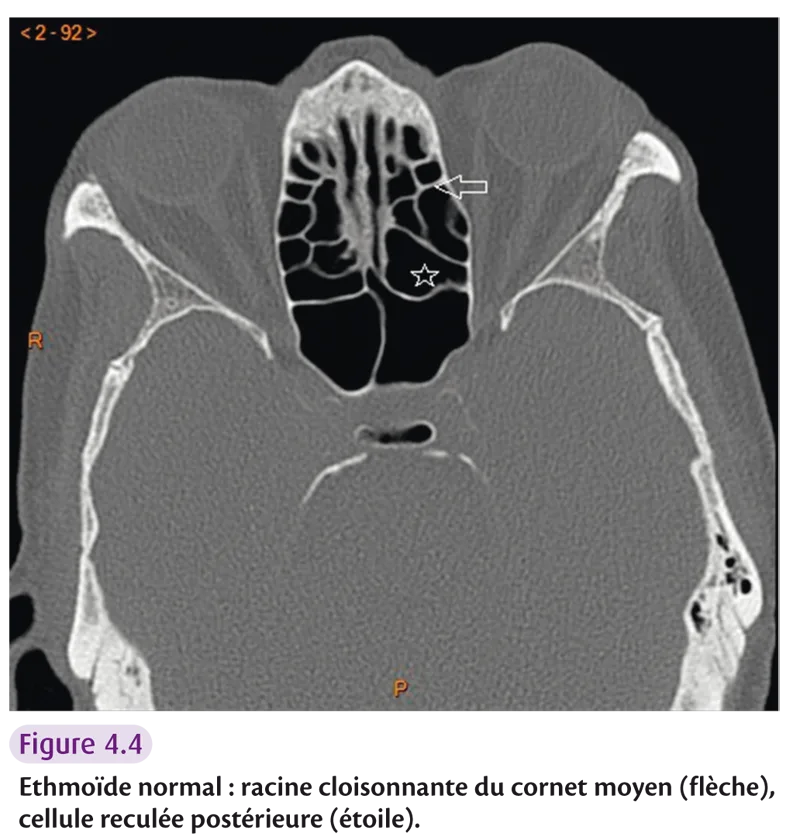

Labyrinthe ethmoïdal

Il est formé de nombreuses cellules, impair et médian (figure 4.4).

Il est constitué par :

une lame verticale et médiane (lame perpendiculaire) qui constitue l’apophyse crista galli en haut et les {2/3} du septum nasal en bas ;

une lame horizontale (lame criblée), orifices de passage des tractus olfactifs ;

deux masses latérales appendues aux bords latéraux de la lame horizontale.

Fig 4.4

Il est divisé en groupe prébullaire (agger nasi) et groupe bullaire. La racine cloisonnante du cornet moyen délimite le groupe postérieur. Les cellules les plus postérieures correspondent aux cellules d’Onodi ou cellules reculées postérieures.